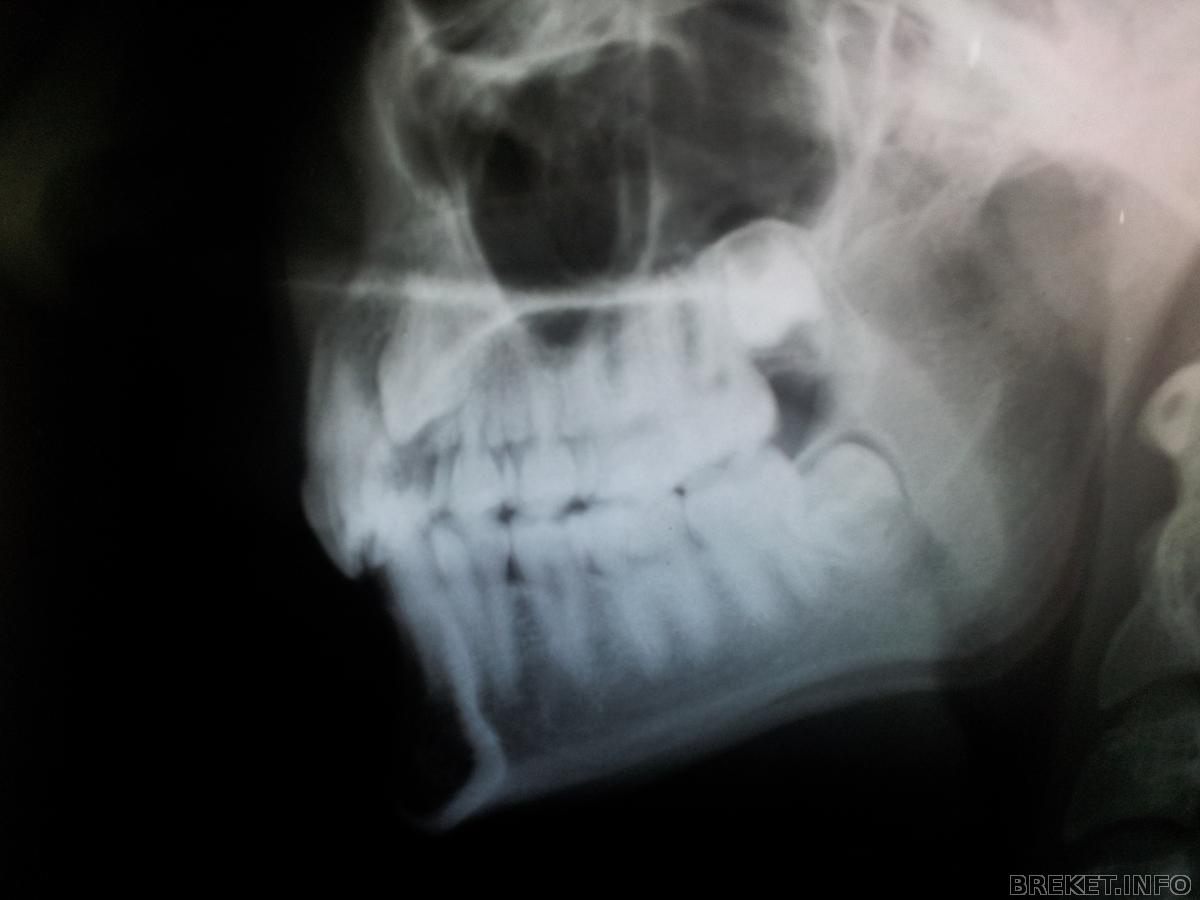

Снимки

Снимки моего клыка.

Да, лежит он очень высоко, но зато хорошо лежит)